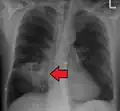

Pulmonary abscess on CT scan -

Lung abscesses are often on one side and single involving posterior segments of the upper lobes and the apical segments of the lower lobes as these areas are gravity dependent when lying down. Presence of air-fluid levels implies rupture into the bronchial tree or rarely growth of gas forming organism.